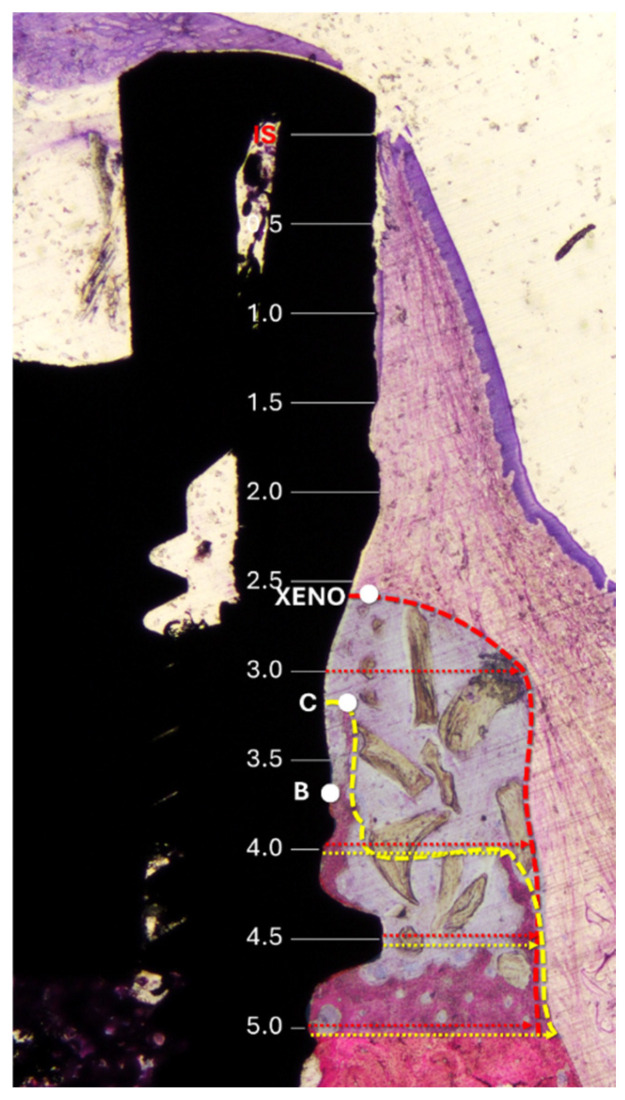

Methods: Six adult Beagle dogs received bilateral extractions of the fourth mandibular premolars. An implant was immediately placed in both the distal alveoli, and standardized buccal bone defects (5 mm height, 3-2 mm width) were prepared. All defects were filled with a slowly resorbing equine xenograft and covered by a resorbable pericardium membrane. At the test sites, the membrane was apically fixed with pins, while no fixation was applied to the control sites. After 3 months of healing, histomorphometric analyses were performed.

Results: The vertical bone gain of the buccal crest was 3.2 mm in the test sites (pin group) and 2.9 mm in the control sites (no-pin) (p > 0.754). No significant difference was found in terms of bone-to-implant contact (BIC). However, residual graft particles were located significantly more coronally in the pin group compared to the no-pin group (p = 0.021). Morphometric analyses revealed similar new bone formation within the groups, but with higher amounts of residual xenograft and soft tissue in the pin group.

Conclusions: Membrane fixation did not significantly enhance vertical bone gain, and although the slightly higher regeneration in the pin group (3.2 mm vs. 2.9 mm) may hold clinical relevance in esthetically sensitive areas and osseointegration, it appeared to limit apical migration of the grafting material.